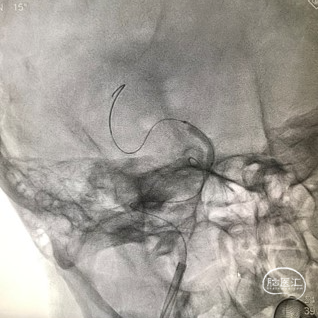

支架通过病变

支架释放